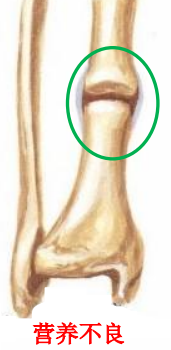

2、营养不良性骨不连

因创伤、医源性损伤等因素导致的骨折端缺血,影响了骨折愈合,可以伴随或不伴随骨缺损。

缺血的骨折块可以与主骨块连接,但是两个彼此缺血的骨块很难连接。

介于增生性骨不连和萎缩性骨不连之间的一个类型,属于二者之间的一个过度状态。